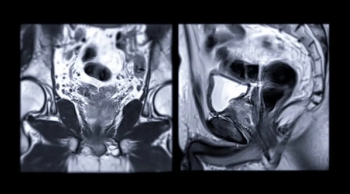

In a new study involving nearly 600 biopsy-naïve men, researchers found that only 4 percent of those with negative prostate MRI had clinically significant prostate cancer after three years of active monitoring.

In patients with PI-RADS 3 lesion assessments, the combination of AI and prostate-specific antigen density (PSAD) level achieved a 78 percent sensitivity and 93 percent negative predictive value for clinically significant prostate cancer (csPCa), according to research presented at the Radiological Society of North American (RSNA) conference.